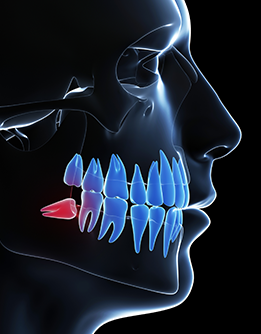

Ağız, Diş ve Çene Cerrahisi

Ağız, diş ve çene cerrahisi, ağız içerisinde yer alan yumuşak ve sert dokularının patolojilerinin tedavi edildiği bilim dalıdır. Gömülü dişlerin çıkarılması veya sürdürülmesi, implant cerrahisi, kist-tümör çıkarılması, çene eklemi (TME) tedavisi ve cerrahisi, tükürük bezi hastalıkları ve cerrahisi, çene-yüz ağrılarının teşhis ve tedavisi, ağız hastalıkları teşhis ve tedavisi, augmentasyon, rekonstrüksiyon operasyonlarını kapsayan ağız, diş ve çene cerrahisi operasyonları lokal veya genel anestezi altında yapılmaktadır.